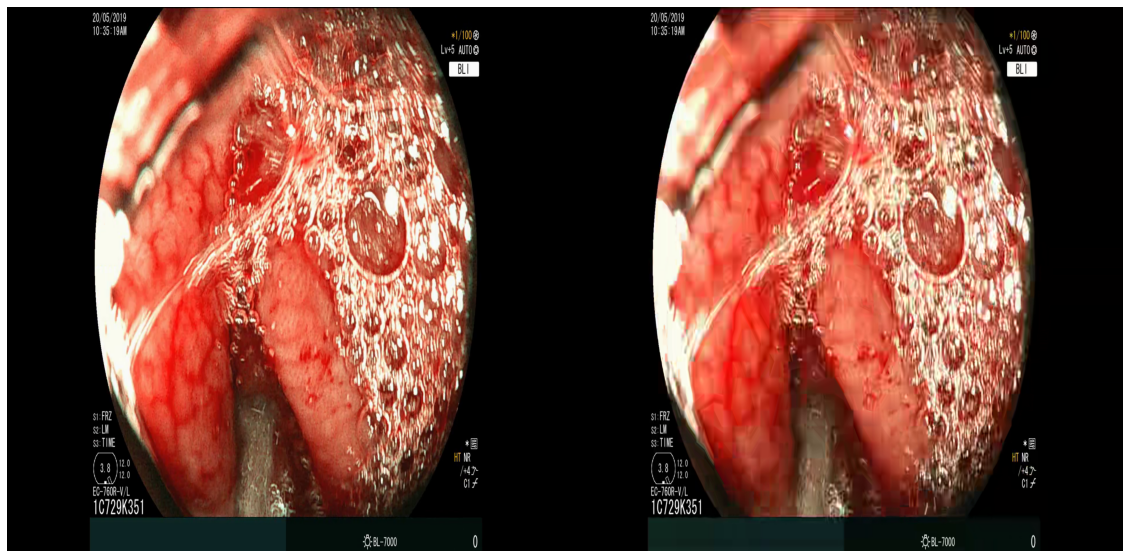

Compression quality: Figure 1 (middle) shows the compression rate versus frame quality distribution for H264 and HEVC. Importantly, we see that H264 and HEVC compress the most medically relvant frames statistically significantly worse: treating each QP value separately, a two-sided Kolmogorov-Smirnov test between distribution of PSNR-CbCr shows that the frame quality is lower for polyp frames than for all frames. For each QP value, , , H264 (HEVC) maximum p-value over all tests is (), mean test statistic (). For the same test with PSNR-Y, see the Appendix. Figure 2 top two rows show the lowest quality compressed frames inside the body according to PSNR-CbCr, with and without polyps (for the absolute worst quality compressed frames, see the Appendix).

A.3 Lowest quality compressed frames